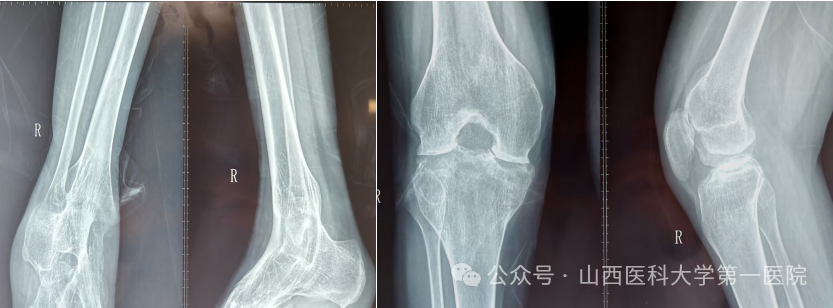

一名42岁的强直性脊柱炎患者,多年来饱受病痛折磨。随着病情进展,双侧髋关节逐渐“锈死”,无法弯腰、下蹲,甚至连坐下都成了奢望——吃饭只能站着,休息只能躺着,生活自理能力几乎丧失。接诊后,骨科杨自权主任团队对患者进行全面检查,发现患者不仅脊柱强直呈“板状腰”,双侧髋关节出现严重融合,而且双膝、双踝关节功能明显下降,手术难度极大。